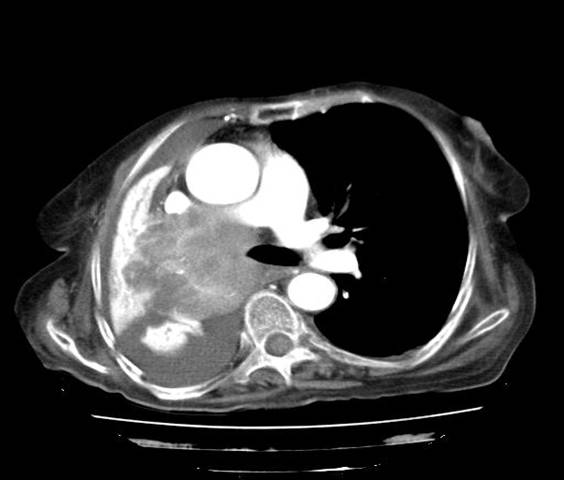

Chest Xray AP view

CT thorax